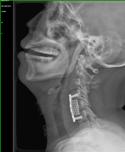

1).C4/5、C5/6间盘突出术前、 术后(C5椎体次全切除,钛笼植入)

2). C5-C6间盘突出术前、 术后(间盘切除,Cage植入)